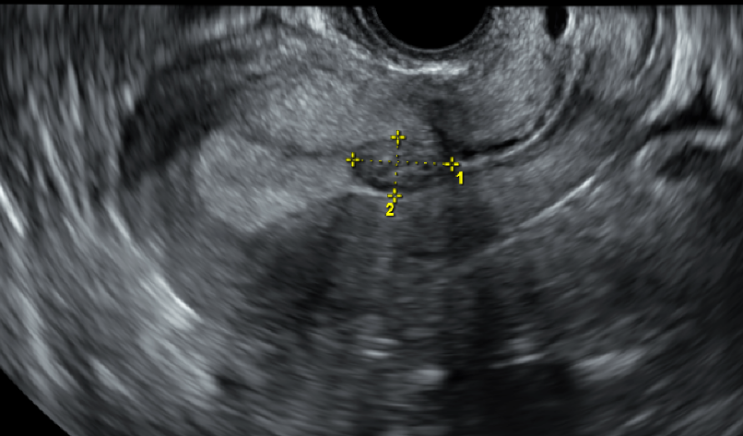

인공주기 동결배아이식시 배란이 되었을 때 - 그대로 진행해도 될까요

동결배아이식은 크게 두 가지 방법으로 진행하게 됩니다. 인공주기 자연주기 인공주기는 여성호르몬을 사용...